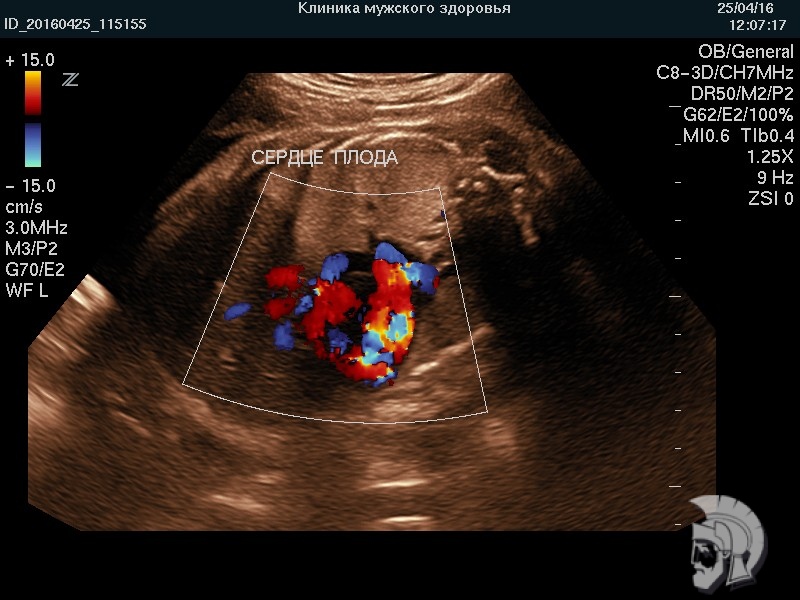

Использование ультразвуковых аппаратов экспертного класса с режимами энергетического допплера и цветового ДОППЛЕРа позволяет врачам Курортной клиники мужского здоровья выявить пороки развития плода, маловодие и многоводие, нарушение МППК угрозу прерывания беременности на самых ранних этапах формирования.

| Фото беременности. Сердце плода 20 недель. Исследование структуры сердца в режиме цветового допплера | ![]() |